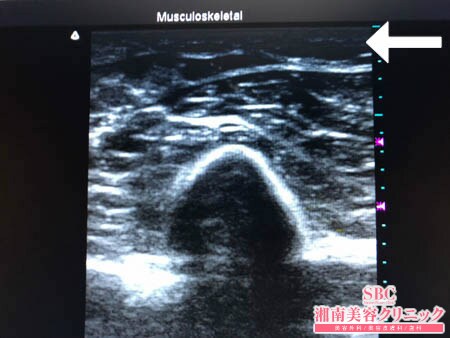

No.206034【脂肪吸引】【動画あり】湘南美容外科脂肪吸引最高責任者である竹田先生による脂肪吸引のフォトギャラリー!スタッフさんからの手術のご依頼は何よりも信頼の証!他院で取り残された二の腕の皮下脂肪をもうひと絞り!術中3Dタッチビュー・左ちからこぶ

決して多くはないものの

皮下脂肪の取り残しを徹底的に

根こそぎ!!

吸引しておきましたので

今回の結果には満足してくださることでしょう。